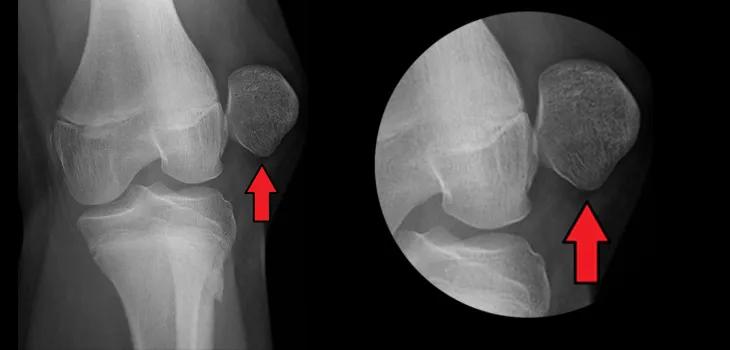

髌骨 是狗狗后腿膝盖处一块形似橄榄球的小骨头,人也有类似的组织 - 就是通常所谓的膝盖骨。髌骨可以在膝盖的滑车沟内上下左右移动,起到润滑保护膝关节、维持膝关节稳定的作用。没有了髌骨,狗狗是无法正常走路的(下图是髌骨外脱臼的X光片)。

髌 骨脱位根据脱离位置分为向内侧偏离的髌骨内脱,以及向外侧偏离的髌骨外脱。